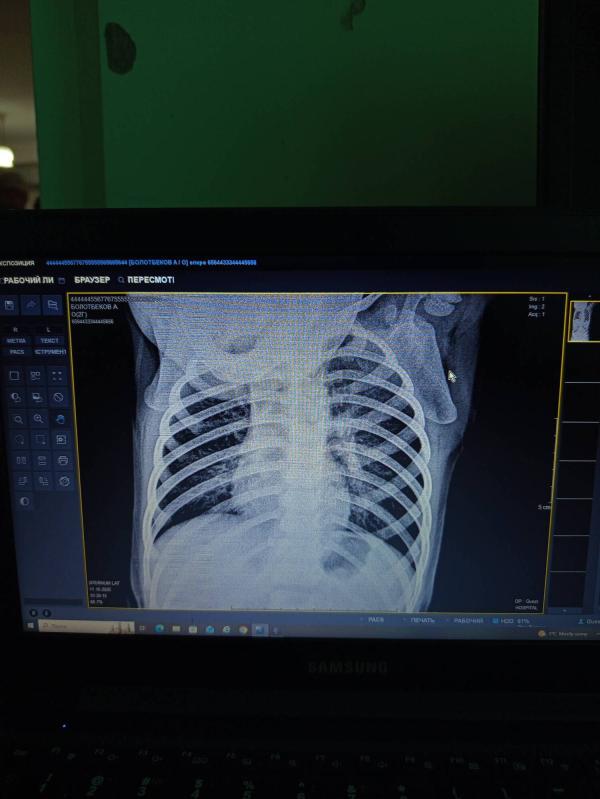

Как определить пневмонию у ребенка: симптомы и диагностика

Кто-нибудь может прочитать что тут написано? Сказали бронхит. Сейчас жду врача. Как лечили бронхит?